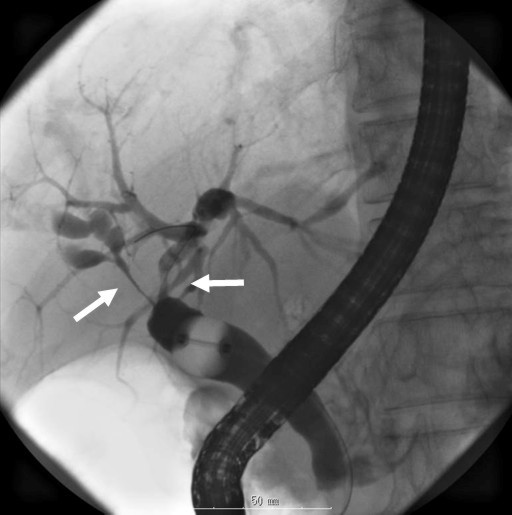

Figure 5. Endoscopic retrograde cholangiography by using a balloon catheter showing a longer stretch of stenosis in the hilar hepatic region (arrows). |

Seven years after clinical onset, abdominal CT revealed multiple pancreatic stones in an atrophic pancreas (Figure 2). ERCP (Figure 3) and magnetic resonance cholangiopancreatography (MRCP) (Figure 3) revealed stenosis of the main pancreatic duct in the head of the pancreas and upstream dilatation. MRCP (Figure 4) and ERC (Figure 5) revealed a longer stretch of stenosis in the hilar hepatic region. We tried steroid therapy in an attempt to ameliorate the stenosis of both the bile duct and the pancreatic duct, and prevent further progression. The initial dose of prednisolone was 30 mg, and this was gradually reduced. Two weeks, 7 weeks, and 11 weeks after the start of prednisolone administration, MRCP revealed no improvement of either the bile duct stenosis or the diffuse irregularity of the main pancreatic duct. The atrophic pancreas showed no change in size. The serum IgG and IgG4 levels decreased from 1,463 to 756 mg/dL (reference range: 870-1,700 mg/dL), and from 127 to 32.9 mg/dL, respectively. The steroid therapy was therefore stopped because of its ineffectiveness and the worsening of diabetes mellitus.